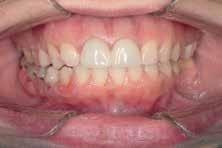

A 33 year old male presented to the orthodontic clinic referred by his prosthodontist . His main concern was the overeruption of maxillary right and left second molar due to bilateral loss of second and third mandibular molars that rendered the placement of prosthodontic implant and crown not possible. The patient had a 4 unit bridge, to replace missing maxillary right first and second premolar, with a root canal treatment and crown done on maxillary right lateral incisor and left second premolar. The patient’s main condition was to reduce the orthodontic system to a minimum with no visible appliances due to the nature of his work in sales.

The patient presented to the clinic every 6 weeks for chain replacement because slow intrusion is needed. The 2nd molar was blocked below the distal contact area of the 1st molar, monitored IPR was carried out between the 1st and 2nd molar on both sides to facilitate the intrusive movement. The treatment took 10 months with 7 appointments.

Case Discussion

The success of maxillary molar intrusion depend on the stability of the miniscrews placed at the appropriate level on the buccal and palatal side to achieve pure intrusive movements. Forces and appointments intervals needed to be adjusted without over loading the teeth or the miniscrews. Nickel Titanium coil springs could have been used for more constant forces acting on the molars but could pose a problem from hygiene and comfort standpoint, for those reasons , pre-stretched elastomeric chains were applied.

Molar protrusion and molar protraction, once regarded as among the most difficult tooth movements to achieve are now successfully performed with the use of orthodontic TADs.

- After 7 months of active intrusion, the level of the 2nd molars was found appropriate, but the intrusion force was maintained as a means of retention for 2 more months.

- During that time, the patient placed 2 implants in the lower posterior edentulous areas (1 on each side)

- Debonding was done, and a thermoformed plastic retainer was manufactured and worn by the patient at all times except at meals to act as retention until the final crowns are placed on the implants which will then prevent relapse of the upper 2nd molars .